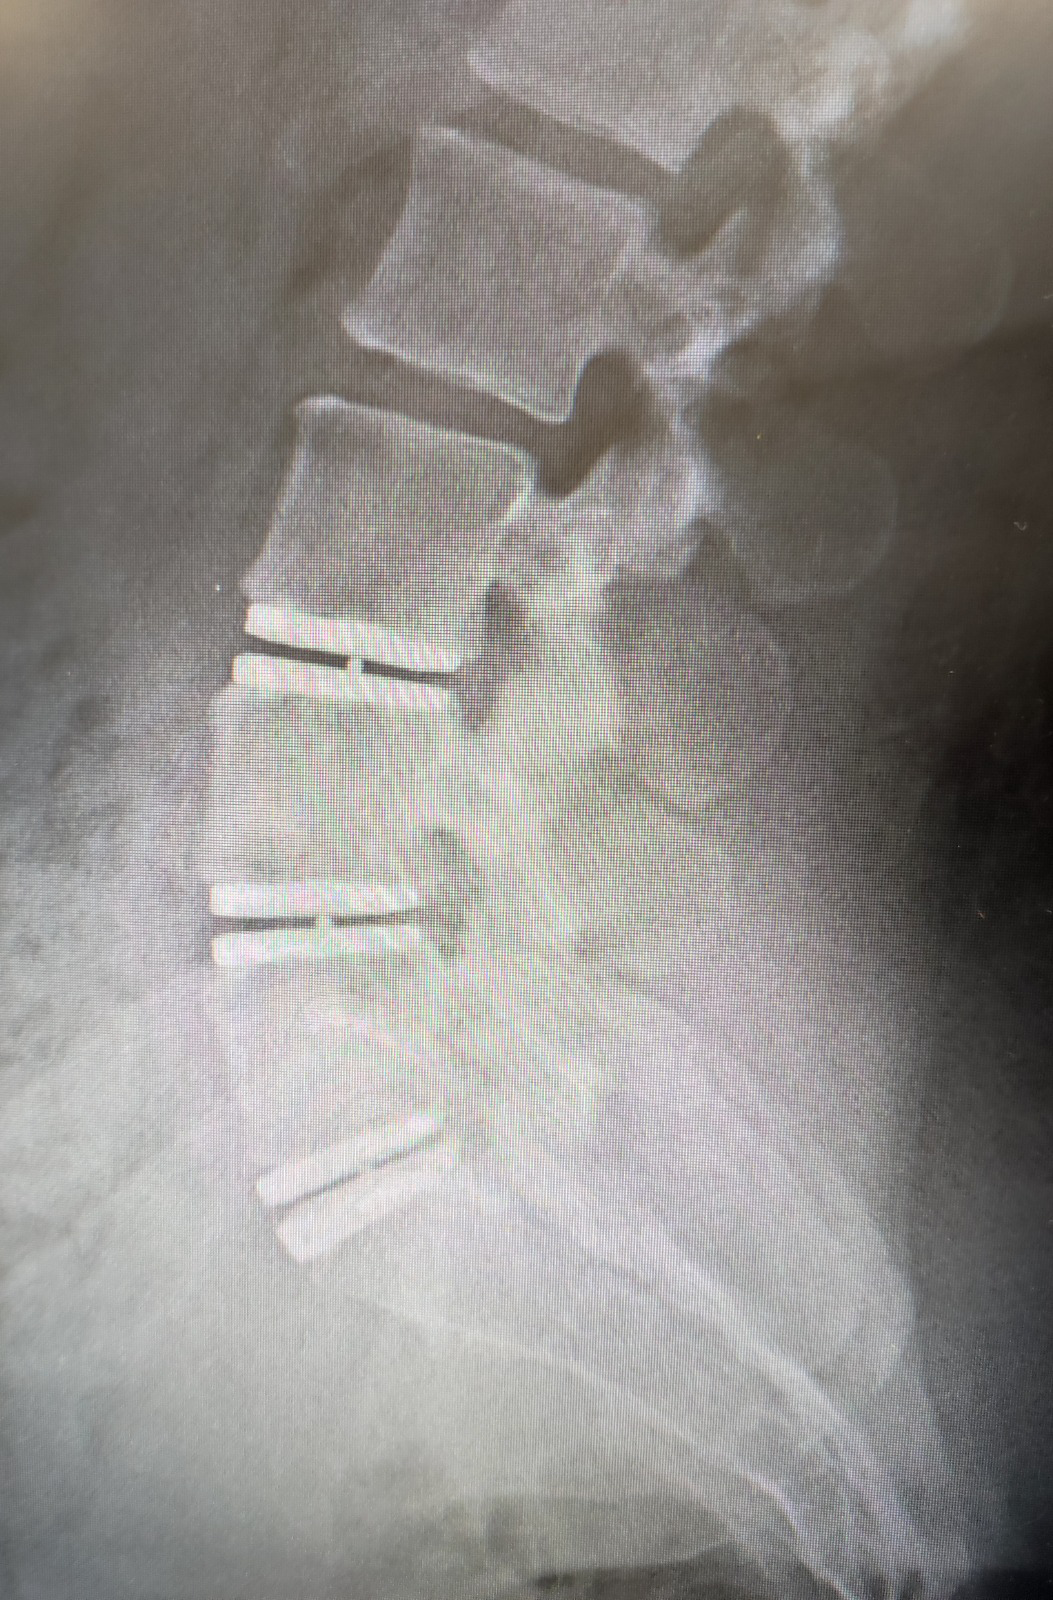

• Prótesis de disco cervical

Un implante de disco en el cuello permite que la columna se mueva con normalidad, como antes de la lesión. En cambio, una cirugía de fusión une los huesos, lo que limita el movimiento.

La prótesis de disco cervical puede restablecer el movimiento natural y el balance sagital normal de la columna mientras la cirugía de fusión no.

• M6

Cirugía de preservación de la movilidad

• Baguera 3 niveles

Motion Preserving

• Baguera 2 niveles